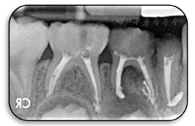

85O,B、84MOD白色样充填物,充填物完整,根尖区黏膜无异常。83无松动,仅余留牙根,牙根断面可见白色样充填物,充填物完整,根尖区黏膜无异常(图2)。

X线影像显示:85根管内阻射影像,达根尖,近中根管根尖有根充物溢出影像,根尖周未见透射影像。84根管内阻射影像,达根尖,远中根尖周有透射影像,波及44恒牙胚硬骨板,近中根尖有根充物溢出影像。83根管内阻射影像,致密,根尖有糊剂溢出,根尖周未见透射影像。73M、D、74MOD、75DO龋洞,发黑,探诊质硬,冷诊未诉不适,叩痛(-),根尖区黏膜无异常(图3)。